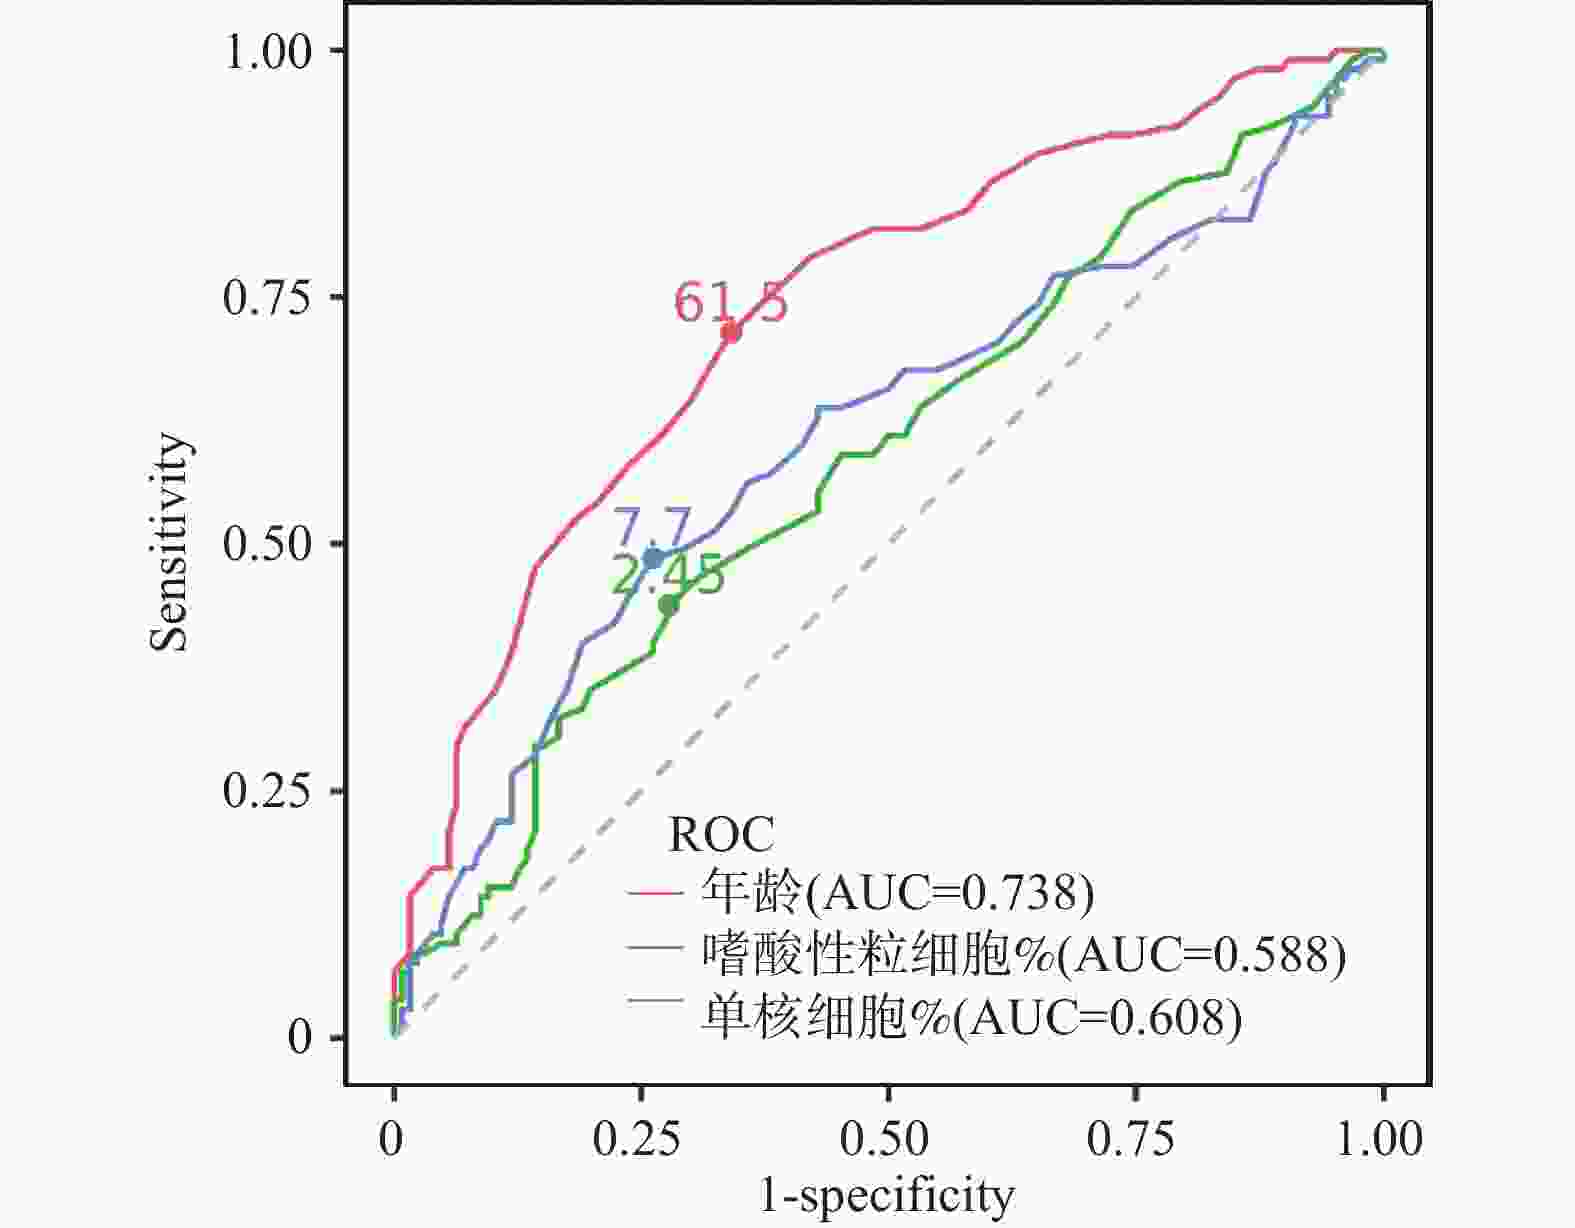

目的 通过心脏磁共振评估基于冠状动脉造影的微循环阻力指数对于冠状动脉微循环障碍的诊断效能,并进一步探究冠状动脉微循环障碍与无症状脑梗死间的相关性。 方法 选取2021年1月至2024年12月期间就诊于昆明医科大学第二附属医院心血管内科的患者231例。通过FlashAngio系统对冠状动脉造影图像左前降支血管进行分析得出caIMR值,以25为界限分为冠状动脉微循环正常组(caIMR<25,n = 126)和冠状动脉微循环障碍组(caIMR≥25,n = 105)。收集所有患者的一般临床资料、实验室指标(血常规、生化全套、糖化血红蛋白)、颅脑CT/MRI结果、心肌微循环磁共振灌注参数(达峰时间(tpeak)、相对峰值信号强度(RSIpeak)、最大上升斜率(Slopemax))、经胸超声心动图常规参数。 结果 (1)50例同时完善CMR和caIMR的患者, caIMR≥25组左前降支支配区域出现了不同程度的tpeak延长,RSIpeak和Slopemax降低,表明caIMR≥25组存在冠状动脉微循环障碍。进行Cohen's Kappa检验一致性分析, Kappa值0.839(P < 0.05),表明caIMR对于CMD的识别具有较高的准确度和评价效果;(2)127例糖尿病患者按照糖化血红蛋白(HbA1c)水平分为血糖控制良好组(4%≤HbA1c<6%)、血糖控制不佳组(6%≤HbA1c<8%)、血糖控制差组(HbA1c≥8%)。40例血糖控制良好组、59例血糖控制不佳组及28例血糖控制差组患者对比,血糖控制不佳组和血糖控制差组caIMR值中位数均高于血糖控制良好组(P < 0.05),且血糖控制不佳组caIMR中位数24.60接近于诊断冠状动脉微循环障碍的caIMR分界值25,血糖控制差组caIMR中位数32.15远高于分界值25;(3)在冠状动脉微循环障碍组中发现很多患者同时存在无症状脑梗死,而在冠状动脉微循环正常组患者中则较少,差异具有统计学意义(P < 0.05)。进一步进行Phi系数相关性分析,Phi系数0.562,差异具有统计学意义(P < 0.001)。提示冠状动脉微循环障碍与无症状脑梗死之间存在相关性。 结论 caIMR对于冠状动脉微循环功能障碍的识别具有较高准确度,且与心脏磁共振的评估效能一致性较高,而在冠状动脉微循环障碍的患者中发现大多同时存在无症状脑梗死,说明心脑微血管两者之间的病变发展可能存在相关性。 Abstract:Objective To evaluate the diagnostic efficacy of coronary angiography-based microcirculatory resistance index for coronary microcirculatory dysfunction through cardiac magnetic resonance (CMR), and further explore the correlation between coronary microcirculatory dysfunction and silent cerebral infarction. Methods 231 patients from the Cardiovasology Department of the Second Affiliated Hospital of Kunming Medical University between January 2021 and December 2024 were selected. The caIMR value of the left anterior descending coronary artery was analyzed using the FlashAngio system, with patients divided into normal coronary microcirculation group (caIMR<25, n = 126) and coronary microcirculatory dysfunction group (caIMR≥25, n = 105). General clinical data, laboratory indicators (complete blood count, biochemical panel, glycated hemoglobin), cranial CT/MRI results, cardiac microcirculatory perfusion MRI parameters (time to peak [tpeak], relative signal intensity at peak [RSIpeak], maximum upslope [Slopemax]), and routine transthoracic echocardiography parameters of all patients were collected. Results (1) Among 50 patients who completed both CMR and caIMR, the caIMR≥25 group showed varying degrees of tpeak prolongation, with reduced RSIpeak and Slopemax, indicating coronary microcirculatory dysfunction. Cohen's Kappa consistency analysis showed a Kappa value of 0.839 (P < 0.05), suggesting high accuracy of caIMR in identifying CMD; (2) 127 diabetic patients were categorized based on HbA1c levels into good glycemic control group (4%≤HbA1c<6%), moderate glycemic control group (6%≤HbA1c<8%), and poor glycemic control group (HbA1c≥8%). Comparing 40 patients in the good control group, 59 in the moderate control group, and 28 in the poor control group, the median caIMR values in the moderate and poor control groups were higher than the good control group (P < 0.05). The moderate control group's median caIMR of 24.60 was close to the diagnostic threshold of 25, while the poor control group's median caIMR of 32.15 was significantly higher; (3) In the coronary microcirculatory dysfunction group, several patients simultaneously had silent cerebral infarction, which was less common in the normal microcirculation group, with statistically significant difference (P < 0.05). Further Phi coefficient correlation analysis showed a coefficient of 0.562, with statistically significant difference (P < 0.001), suggesting a correlation between coronary microcirculatory dysfunction and silent cerebral infarction. Conclusion caIMR demonstrates high accuracy in identifying coronary microcirculatory dysfunction, with good consistency with CMR assessment. The high prevalence of silent cerebral infarction in patients with coronary microcirculatory dysfunction suggests potential interconnected pathological development in cerebral and cardiac microvascular systems. -

项目 SBI 非SBI 总计 CMD 78 27 105 非CMD 23 103 126 总计 101 130 231 Phi系数:0.562(P < 0.001);Phi系数>0.5表示具有较强相关性;P < 0.05。 表 8 预测CMD发生的诊断价值

Table 8. Diagnostic value for predicting the occurrence of CMD

危险因素 曲线下面积 灵敏度 特异度 约登指数 95%CI P 年龄 0.738 0.714 0.659 0.373 0.674~0.803 <0.001* MONO% 0.608 0.486 0.738 0.160 0.533~0.683 0.005* EO% 0.588 0.438 0.722 0.224 0.514~0.662 0.020* *P < 0.05。 表 9 caIMR<25组与caIMR≥25组tpeak比较[M(P25,P75)]